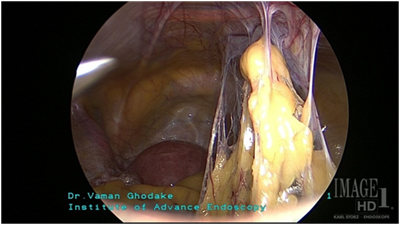

bicornuate uterus

ऑपरेशनपूर्वी